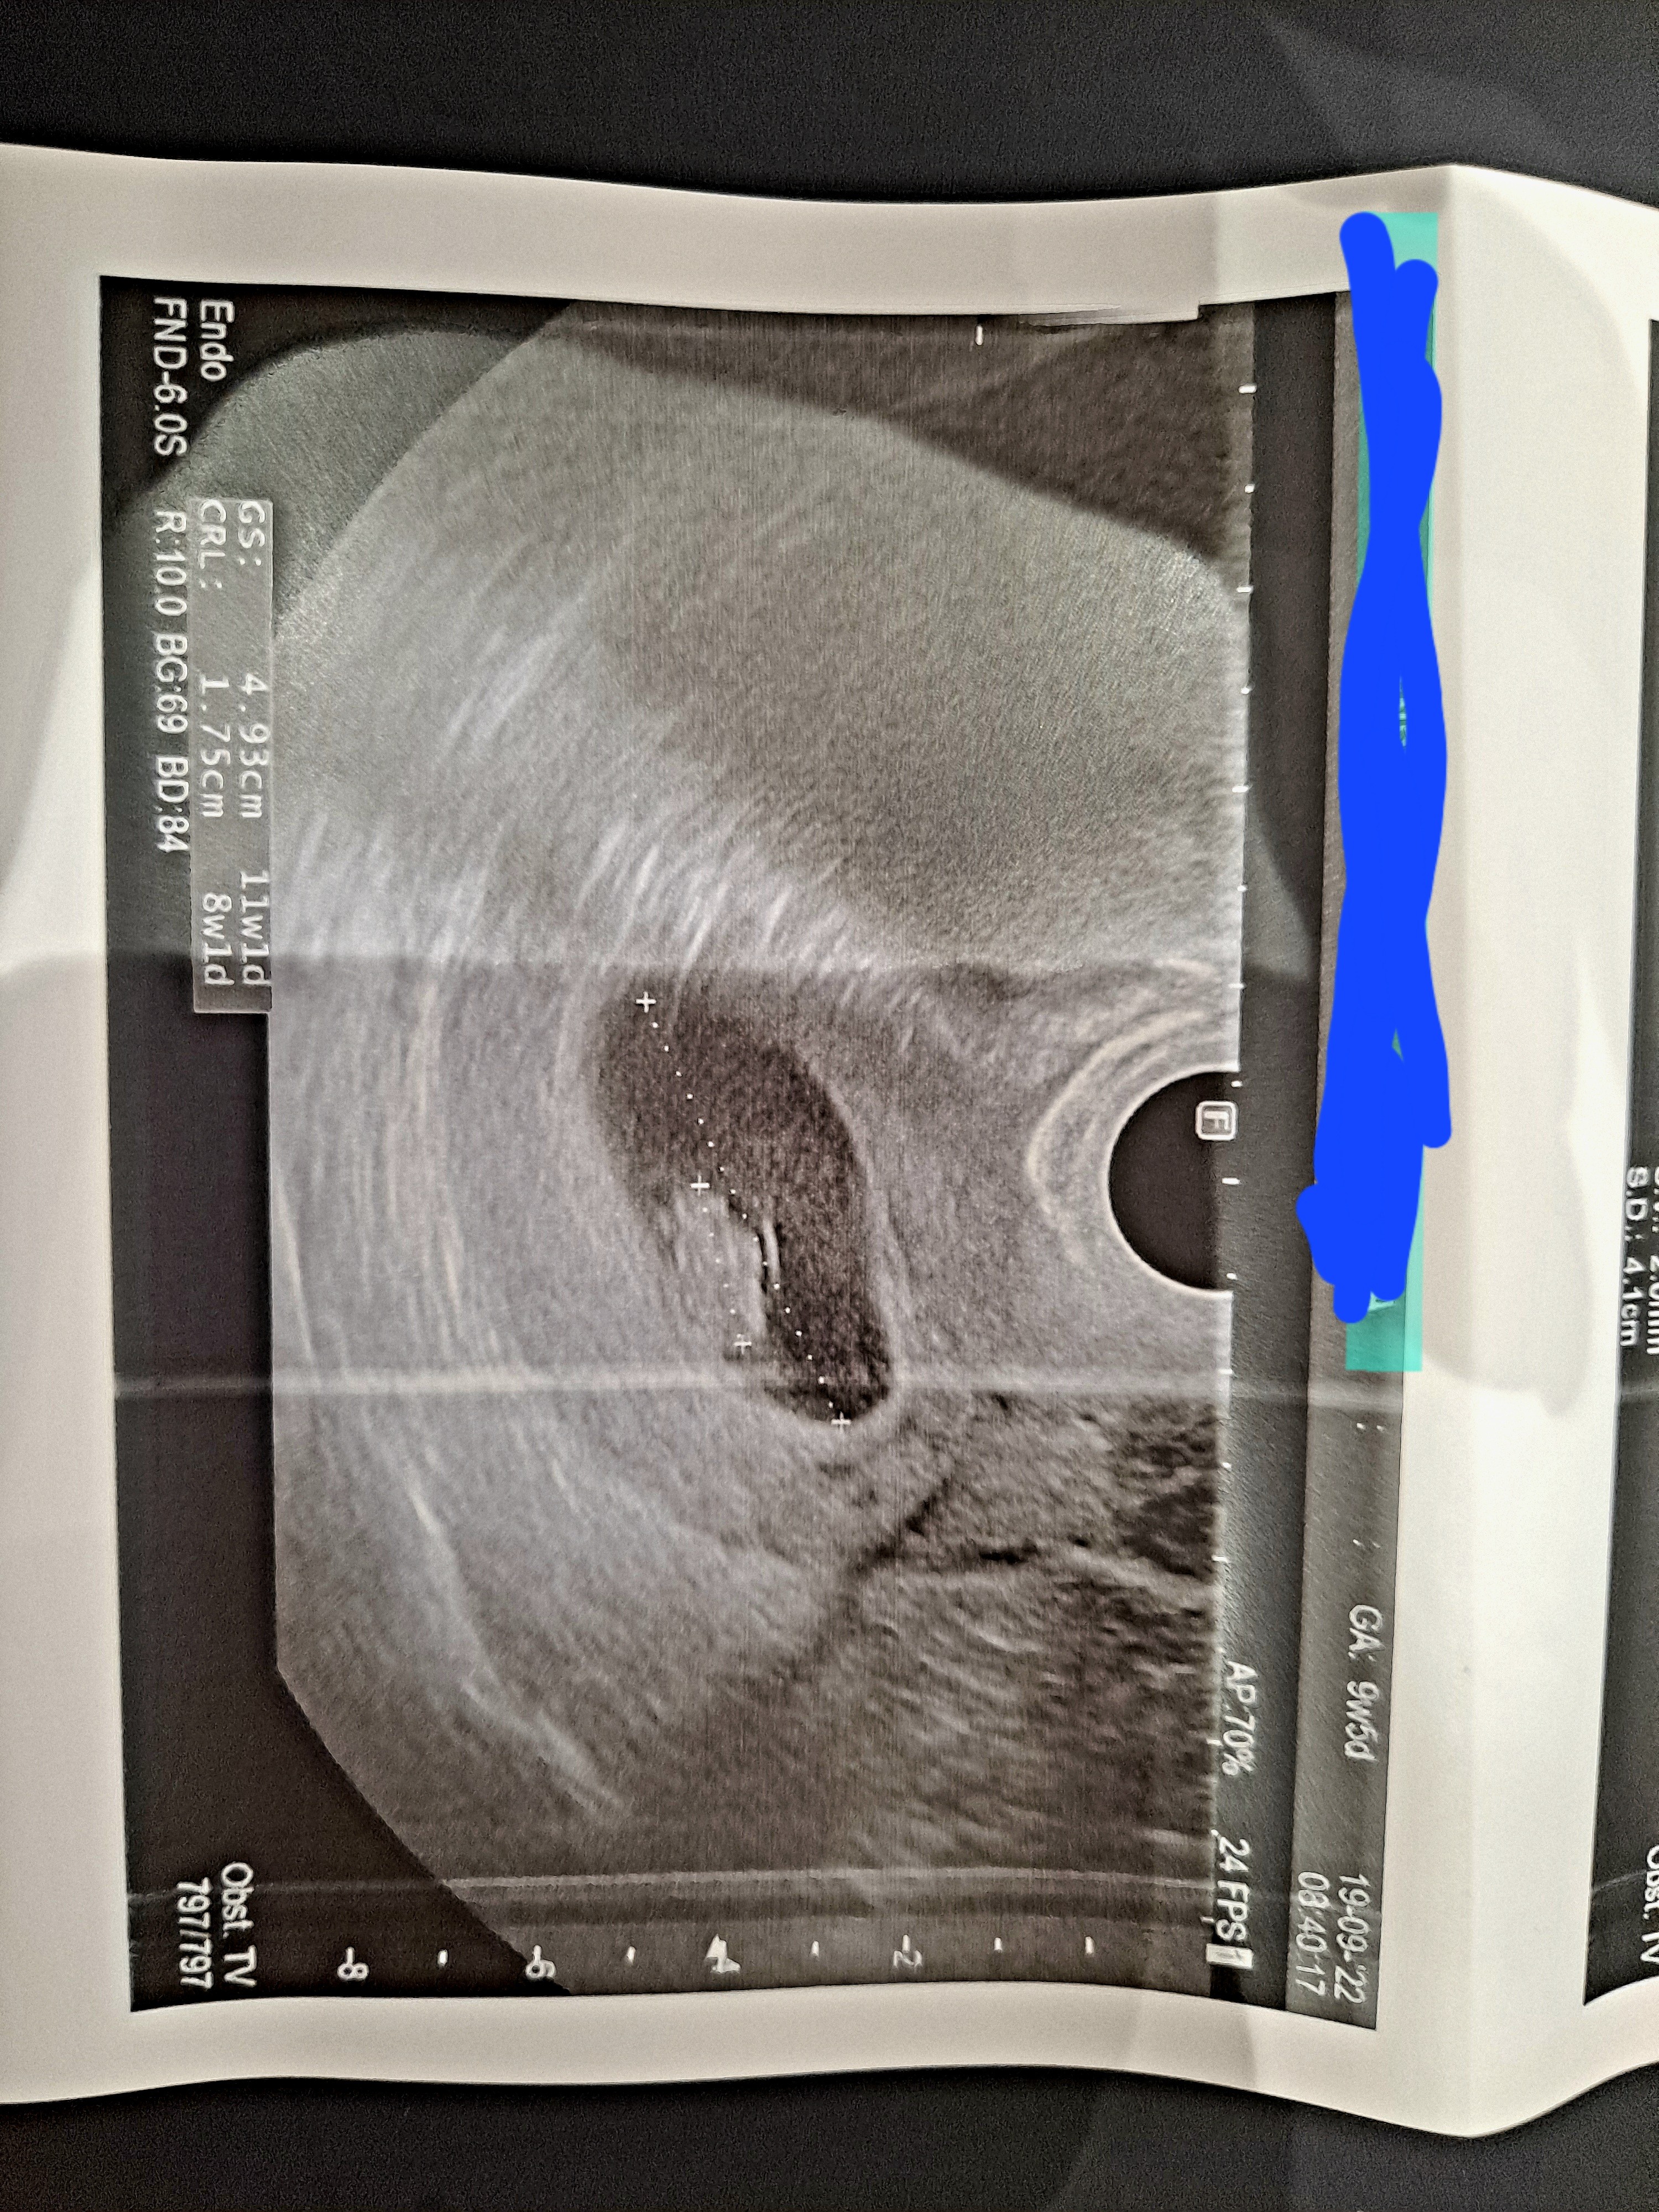

• 20220919_100226.jpg

20220919_100226.jpg

3,1 MB · Wyświetleń: 98

Właśnie nie wiem bo na usg jest napisane 9+5

To na pewno wg OM jest wyliczone. Lekarz na początku badania wprowadza dane do komputera i to przelicza termin wg miesiączki. Generalnie wielkość dziecka to pomiar z USG. Ja w poprzedniej ciąży miałam rozjazd 2 dni, teraz na pierwszej wizycie różnica chyba 4, ale też było baaardzo wcześnie, ledwo widoczne serduszko i miałam też minimalnie dłuższe cykle. W poprzedniej ciąży też na początku ciąża młodsza, potem starsza niż OM i syn szedł tym trybem starszego dziecka, a urodził się całkiem spory jak na moje gabaryty 🤷🏻‍♀️